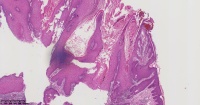

角化棘皮瘤?

性别

男

年龄

45岁

临床诊断

一般病史

面部包块

标本名称

图1

倾向脂溢性角化病。